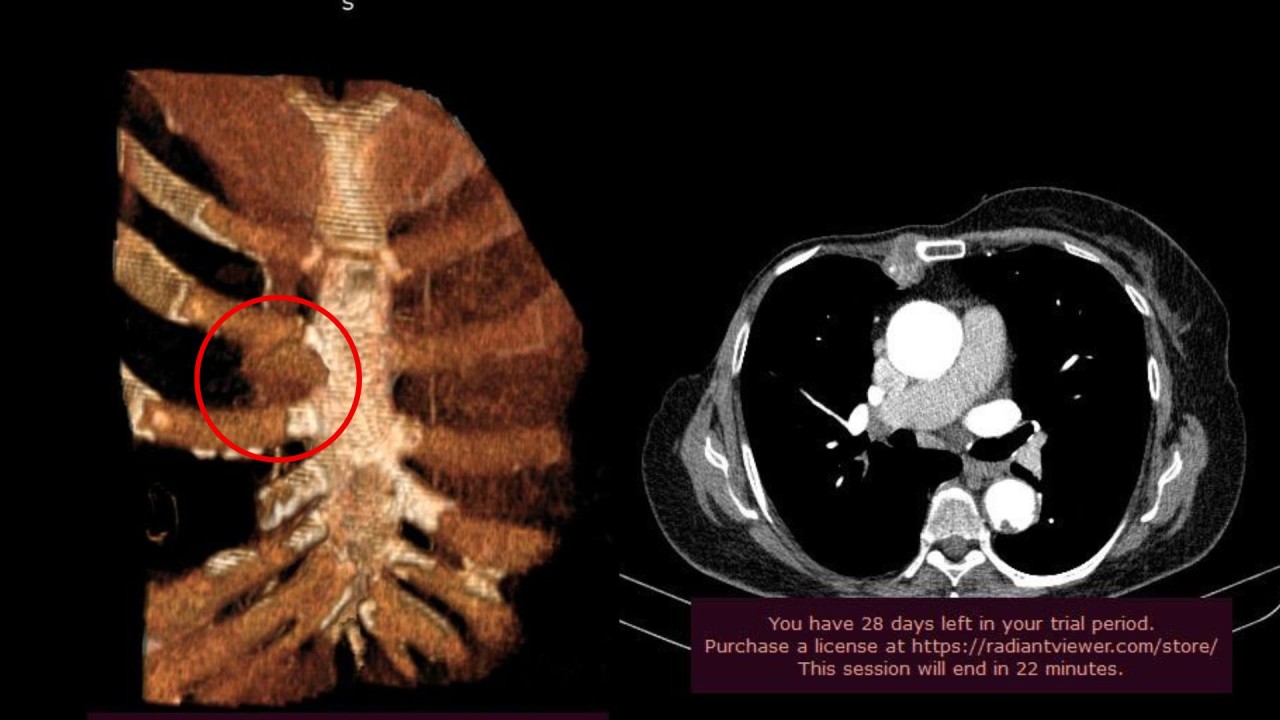

Այցի շրջանակում պրոֆեսոր Ուոնգը և ՈՒԱԿ Կրծքավանդակային վիրաբուժության և ինտերվենցիոն թոքաբանության բաժանմունքի վարիչ, թորակալ վիրաբույժ Տիգրան Բյուզանդյանը կատարել են համատեղ վիրահատական միջամտություն՝ կրծքավանդակի պատի մասնատում` 2-րդ, 3-րդ և 4-րդ կողոսկրերի և կրծոսկրի մասնահատումով, ուռուցքի հեռացումով, պլաստիկայով։